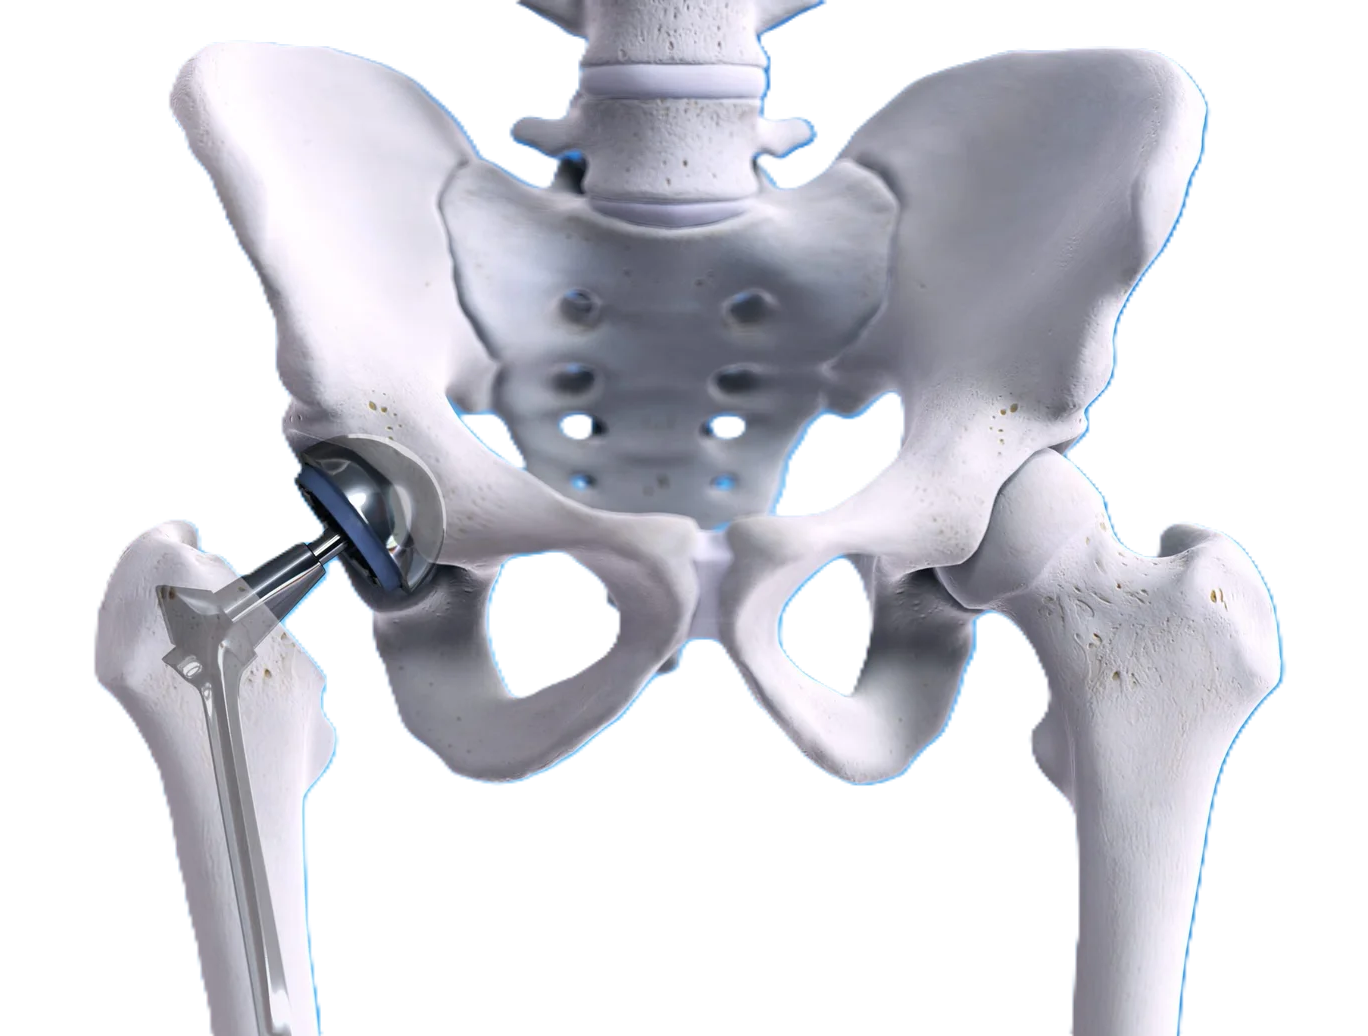

Devamını OkuProtez ameliyatları eklemdeki ilerlemiş kireçlenmelerin yol açtığı ağrı ve hareket kısıtlılığının eklem yüzlerinin metal implantlarla ( protez ) değiştirilerek eski sağlığınıza kavuşmanızı sağlayan uygulamalardır.

Protez cerrahileri, artroskopik girişimler, kırık ve deformite cerrahileri; eklem biyomekaniği, yük dağılımı ve yumuşak doku dengesi esas alınarak planlanır. Cerrahi karar sürecinde yalnızca radyolojik bulgular değil; hastanın klinik yakınmaları, fonksiyon kaybı ve yaşam kalitesine etkisi birlikte değerlendirilir. Modern ortopedik cerrahinin temel hedefi; en az invaziv yöntemle en yüksek fonksiyonel kazanımı sağlamaktır.